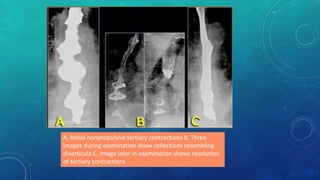

A. Initial nonpropulsive tertiary contractions B. Three

images during examination show collections resembling

diverticula C. Image later in examination shows resolution

of tertiary contractions